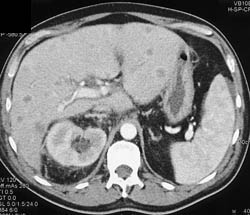

Liver Metastases